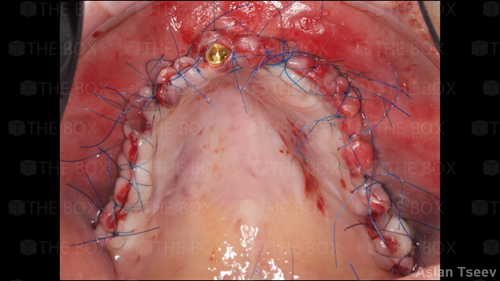

A new case was made public by Jean-Claude Imber check it out here.